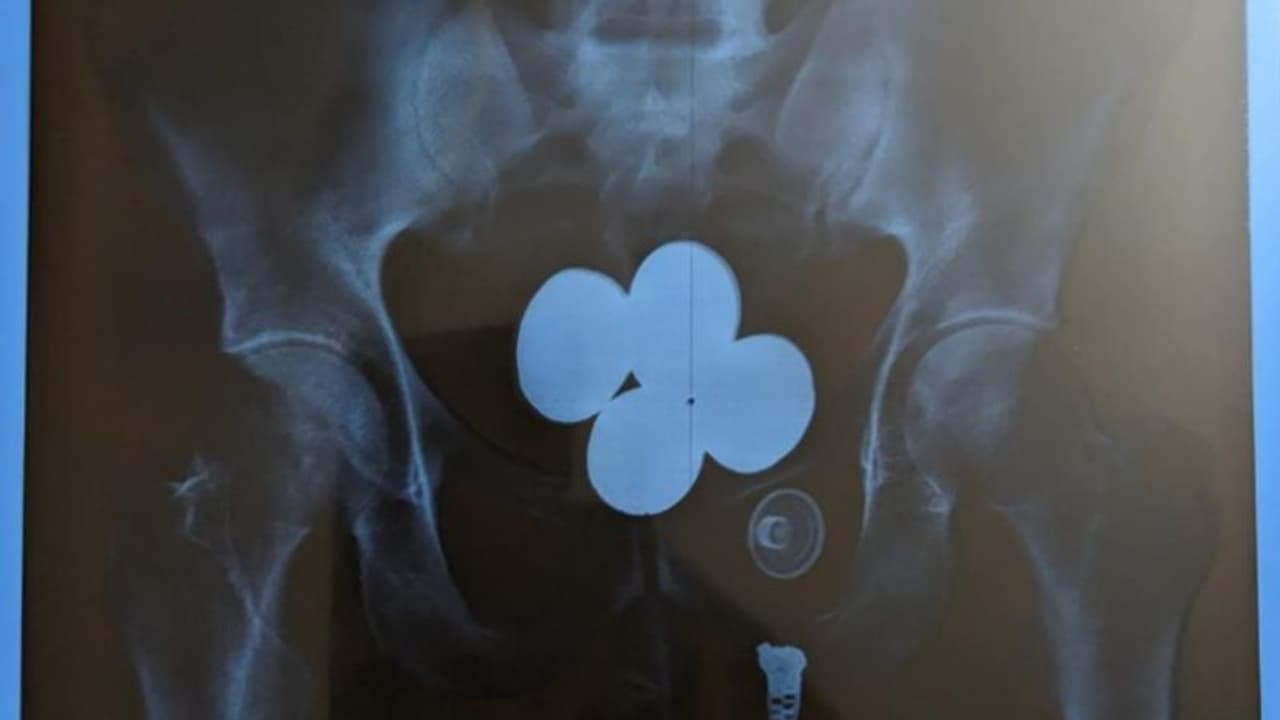

പൊലീസ് കസ്റ്റഡിയിൽ സ്വർണക്കടത്ത് ആവർത്തിച്ച് നിഷേധിച്ച ഉദയ് അവസാനം പിടിയിലായത് എക്സ് റേ പരിശോധനയിലാണ്

ആകെ 58 ലക്ഷം രൂപ മൂല്യം വരുന്ന 24 കാരറ്റ് 957.2 ഗ്രാം സ്വര്ണ്ണമാണ് ഇയാളിൽ നിന്ന് പൊലീസ് കണ്ടെത്തിയത്. സംഭവത്തിന് പിന്നാലെ 30കാരനായ ഉദയ് പ്രകാശിന്റെ അറസ്റ്റും പൊലീസ് രേഖപ്പെടുത്തി. സ്വര്ണ്ണം മിശ്രിത രൂപത്തില് നാല് കാപ്സ്യൂളുകളാക്കി ശരീരത്തിനുള്ളില് ഒളിപ്പിച്ചാണ് ഇയാള് ഷാര്ജയില് നിന്നും കടത്തിയത്.

വിമാനത്താവളത്തിന് പുറത്തെത്തിയ ഉദയ് പ്രകാശിനെ പൊലീസ് കസ്റ്റഡിയിലെടുത്തു. തന്റെ പക്കല് സ്വര്ണ്ണമുണ്ടെന്ന കാര്യം ഉദയ് എത്ര ചോദ്യം ചെയ്തിട്ടും സമ്മതിച്ചില്ല. പ്രതിയുടെ പക്കലുണ്ടായിരുന്ന ബാഗുകൾ പൊലീസ് പരിശോധിച്ചെങ്കിലും സ്വർണം കണ്ടെത്താനായില്ല. പിന്നീട് പൊലീസ് കസ്റ്റഡിയിൽ ഇയാളെ വിശദമായ വൈദ്യ പരിശോധനക്ക് വിധേയമാക്കി. മെഡിക്കൽ എക്സ് റേ പരിശോധനയിൽ ഉദയുടെ വയറിനകത്ത് 4 കാപ്സ്യൂളുകള് ദൃശ്യമായി. പിടിച്ചെടുത്ത ഈ സ്വര്ണ്ണം കോടതിയില് സമര്പ്പിക്കും. തുടരന്വേഷണത്തിനായി വിശദമായ റിപ്പോര്ട്ട് കസ്റ്റംസിനും സമര്പ്പിക്കുമെന്ന് ജില്ലാ പൊലീസ് മേധാവി അറിയിച്ചു.